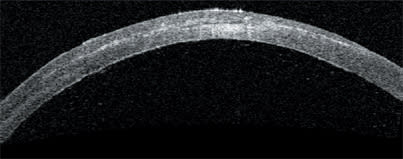

Depicting density, the color version of the anterior-segment scan shows lower amplitudes as blue colors and larger amplitudes as red colors.

The color version of the high-resolution corneal scan shows the useful light coming through the implant's aperture and the scattered light coming through the implant's fenestrations.

As this implant was being developed, the Visante OCT allowed documentation of the amount of scattered light coming through the implant's fenestrations. This allowed researchers to determine what level of light passing through caused glare and reduced contrast and what level did not affect patients' contrast sensitivity. OM